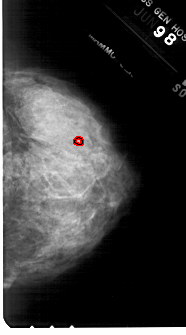

A_1845_1.RIGHT_CC

RIGHT_CC LINES 5011 PIXELS_PER_LINE 2776 BITS_PER_PIXEL 12 RESOLUTION 43.5 OVERLAY

FILE: A_1845_1.RIGHT_CC.OVERLAY

TOTAL_ABNORMALITIES 1

ABNORMALITY 1

LESION_TYPE CALCIFICATION TYPE PUNCTATE DISTRIBUTION CLUSTERED

ASSESSMENT 4

SUBTLETY 1

PATHOLOGY BENIGN

TOTAL_OUTLINES 1

BOUNDARY